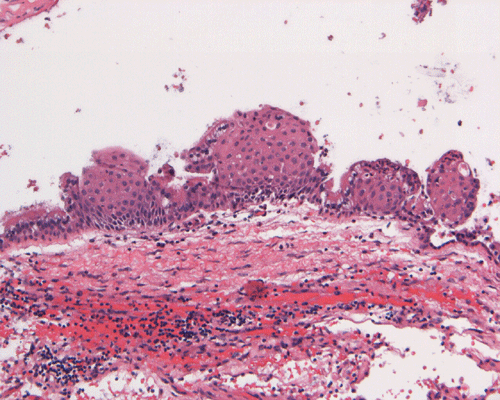

Clinical informationThe patient was a 45 year-old man who presented with staring episode that is reminiscent of a seizure. MRI examination disclosed a cystic sellar mass that deflected his optic nerve. There was no clear visual loss.

Com403-1-MRI1.gif (175407 bytes) Com403-1-2.gif (140093 bytes) Com403-1-4.gif (125178 bytes) Com403-1-1.gif (139689 bytes) Com403-1-3.gif (145349 bytes)

What is your diagnosis? Discussion